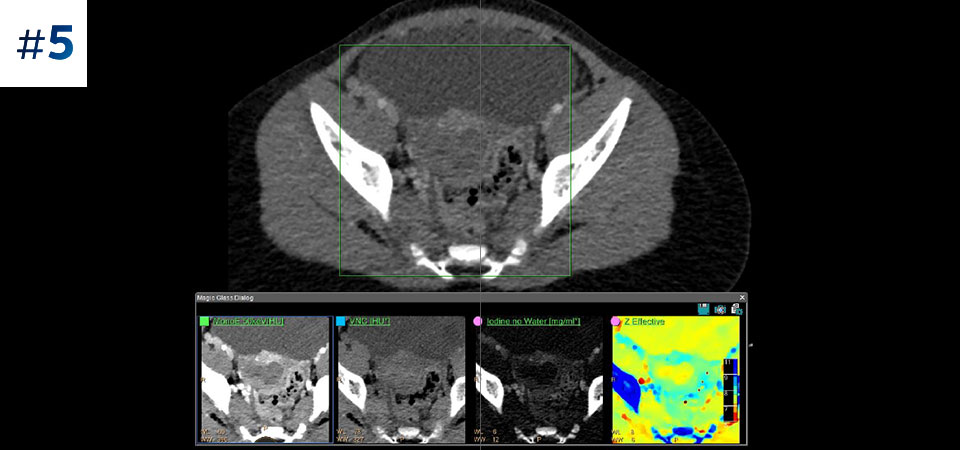

With detector-based spectral, you acquire multiple layers of data—conventional and spectral—within a single exposure and without special scan modes for improved tissue characterization and visualization.

Scan as usual A single scan for fast, low-dose conventional and spectral data for every patient, every time.

Always available 100% spectral, 100% of the time for results that are always available on-demand, even retrospectively.

Reduced follow-up exams Improved tissue characterization and visualization may reduce the need for follow-up scanning for sub-optimal exams and incidental findings.